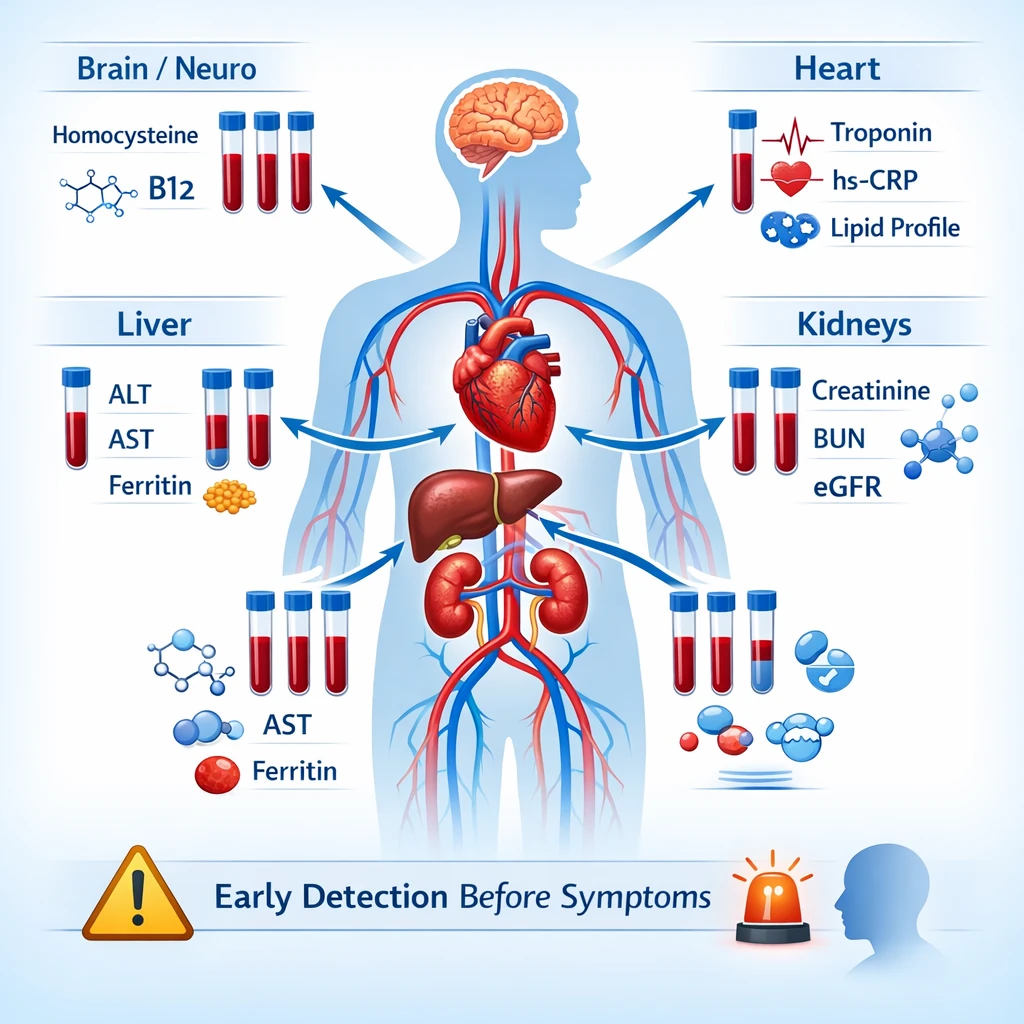

نشانگرهای بیوشیمیایی مرتبط با آسیب زودهنگام اندامهای حیاتی

۱. کبد؛ آسیب خاموش اما قابلتشخیص

کبد توانایی بالایی در جبران دارد و اغلب بدون علامت آسیب میبیند.

نشانگرهای خونی مهم:

- افزایش ALT و AST (حتی خفیف)

- بالا رفتن GGT

- تریگلیسرید بالا

- نسبت غیرطبیعی AST/ALT

این الگوها میتوانند نشانه اولیه کبد چرب غیرالکلی، التهاب کبد یا استرس متابولیک باشند.

۲. کلیهها؛ افت عملکرد پیش از علائم

آسیب کلیه معمولاً دیر علامتدار میشود.

شاخصهای کلیدی:

- افزایش کراتینین سرم (حتی لب مرز)

- کاهش eGFR

- افزایش اوره خون

- وجود آلبومین در ادرار (میکروآلبومینوری)

این تغییرات ممکن است سالها قبل از ورم یا افزایش فشار خون دیده شوند.

۳. قلب و عروق؛ هشدارهای زودهنگام در خون

بیماریهای قلبی اغلب از عروق شروع میشوند.

نشانگرهای مهم:

- LDL بالا یا HDL پایین

- تریگلیسرید بالا

- افزایش hs-CRP (التهاب عروقی)

- افزایش خفیف تروپونین در شرایط خاص

این تغییرات نشاندهنده افزایش خطر بیماری قلبی حتی در افراد بدون علامت هستند.

۵. مغز و سیستم عصبی؛ آسیبهای متابولیک پنهان

برخی اختلالات عصبی ریشه بیوشیمیایی دارند.

نشانگرهای مهم:

- کمبود ویتامین B12

- افزایش هموسیستئین

- اختلالات تیروئیدی (TSH غیرطبیعی)

این تغییرات میتوانند پیشزمینه اختلالات شناختی، افسردگی یا نوروپاتی باشند.